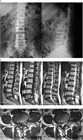

1. 男性に多く(2~3:1)、好発年齢は20~40歳代が中心で、好発レベルとしてはL4/5、L5/S、である(ガイドライン推奨grade C)。

1. ヘルニアのサイズが大きいものや、遊離脱出したものや、MRIでリング状に造影されるものは高率に自然退縮する(ガイドライン推奨grade B)。